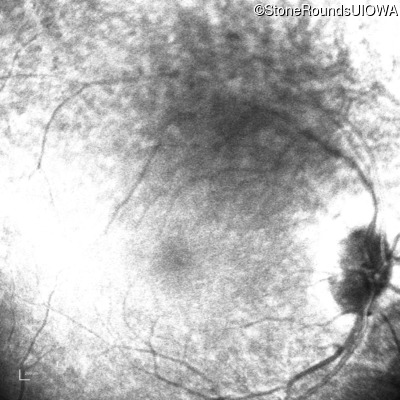

SECORD (IA2b)

Age at visit:

26 years

OD

OS

1/700 sc

SECORD

RPGRIP1

His631Arg CAC>CGC

Pro237 del1ccA

AR